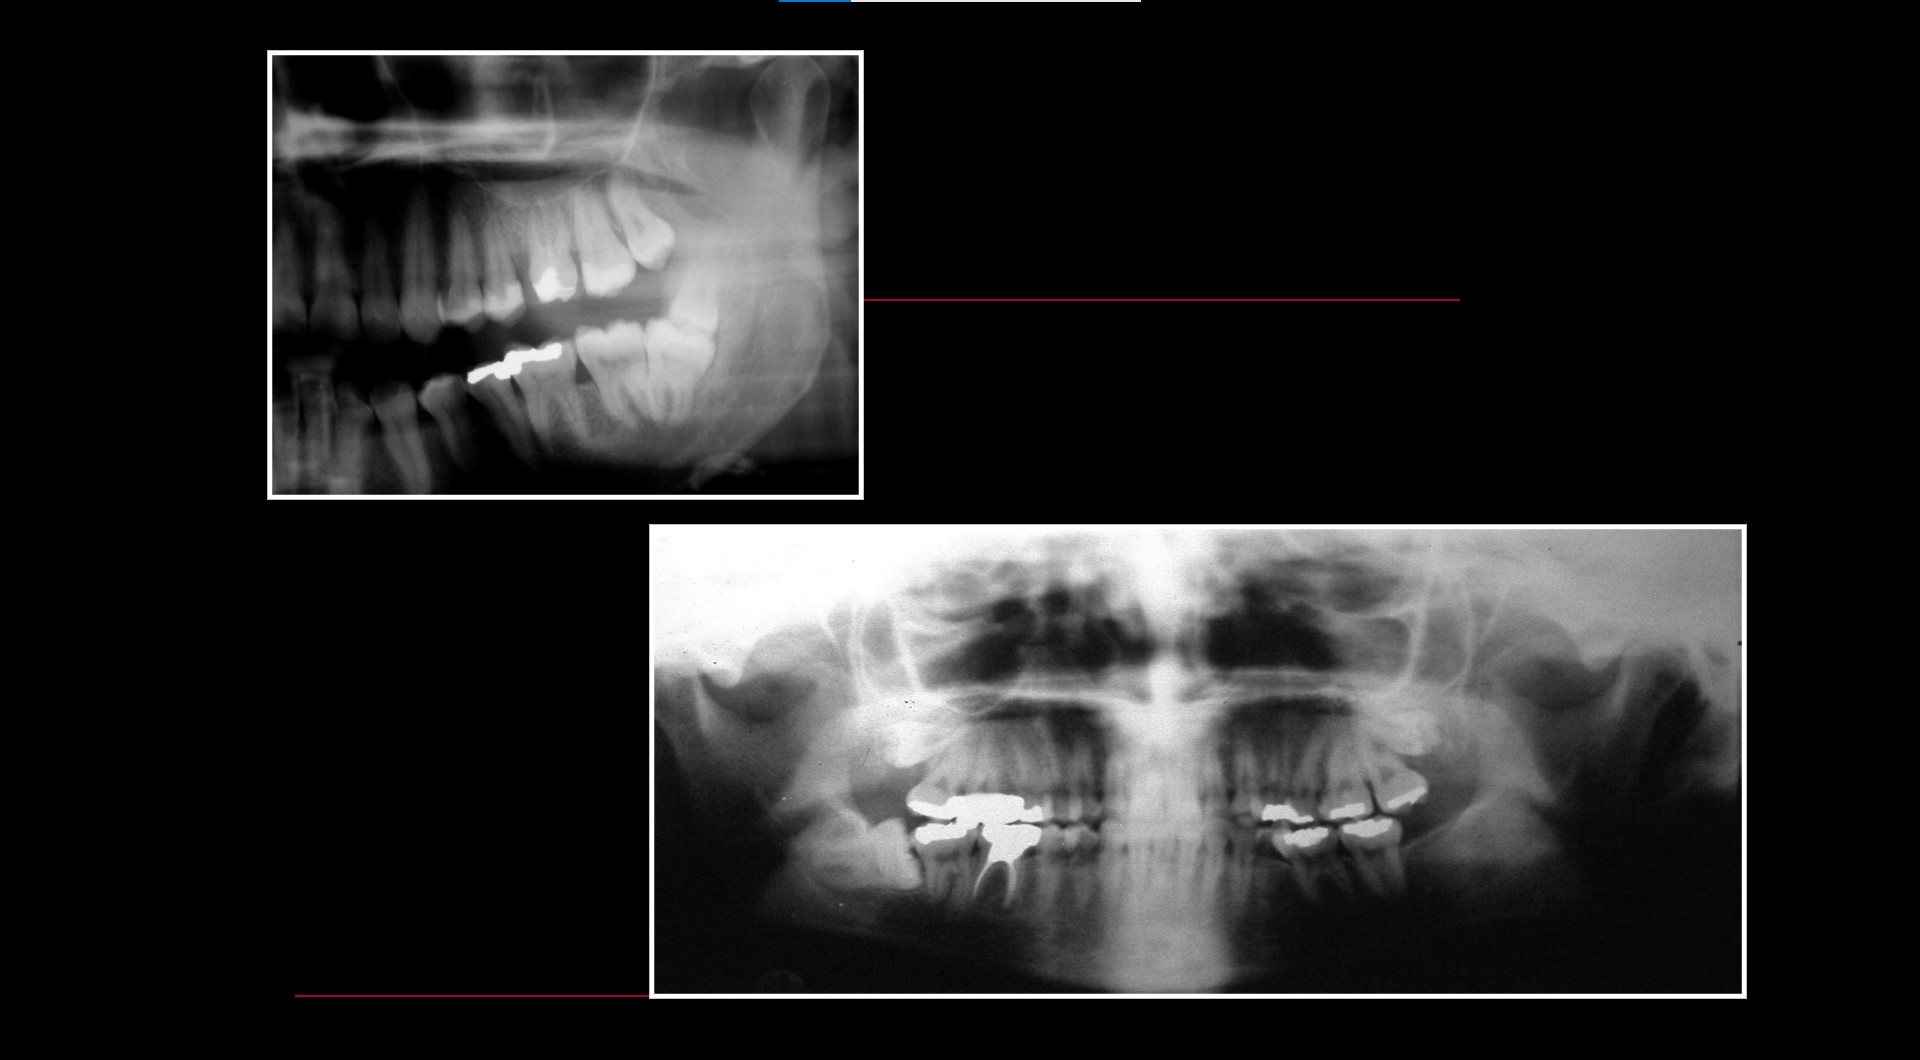

Impacted teeth

Relationship between Fractures of Mandibular Angle and the Presence of a Lower Third Molar